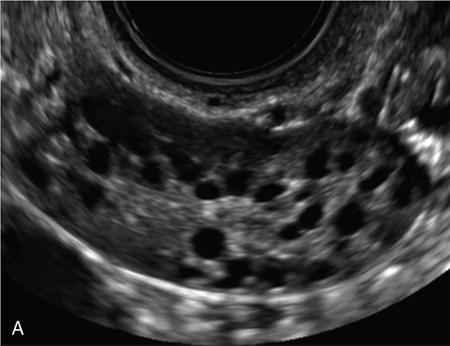

1. 1. Real-time 2D-US – routine standard technique

• Average number of follicles in longitudinal and transverse planes is determined (Fig. 11.20.1.2).

• Antral follicle size is determined by two perpendicular diameters.

• Useful to differentiate intraovarian and paraovarian structures (assessment of whether structures ‘slide’ on application of pressure by probe)

• Useful to differentiate small follicle from vessel (with application of Doppler)

• Relatively long scan time

• Does not allow offline analysis, which would be useful for training, to resolve uncertainties and for audit purposes

Image

Fig. 11.20.1.2 (A) Antral follicles by 2D USG without harmonics. (B) Antral follicles by 2D USG with harmonics.